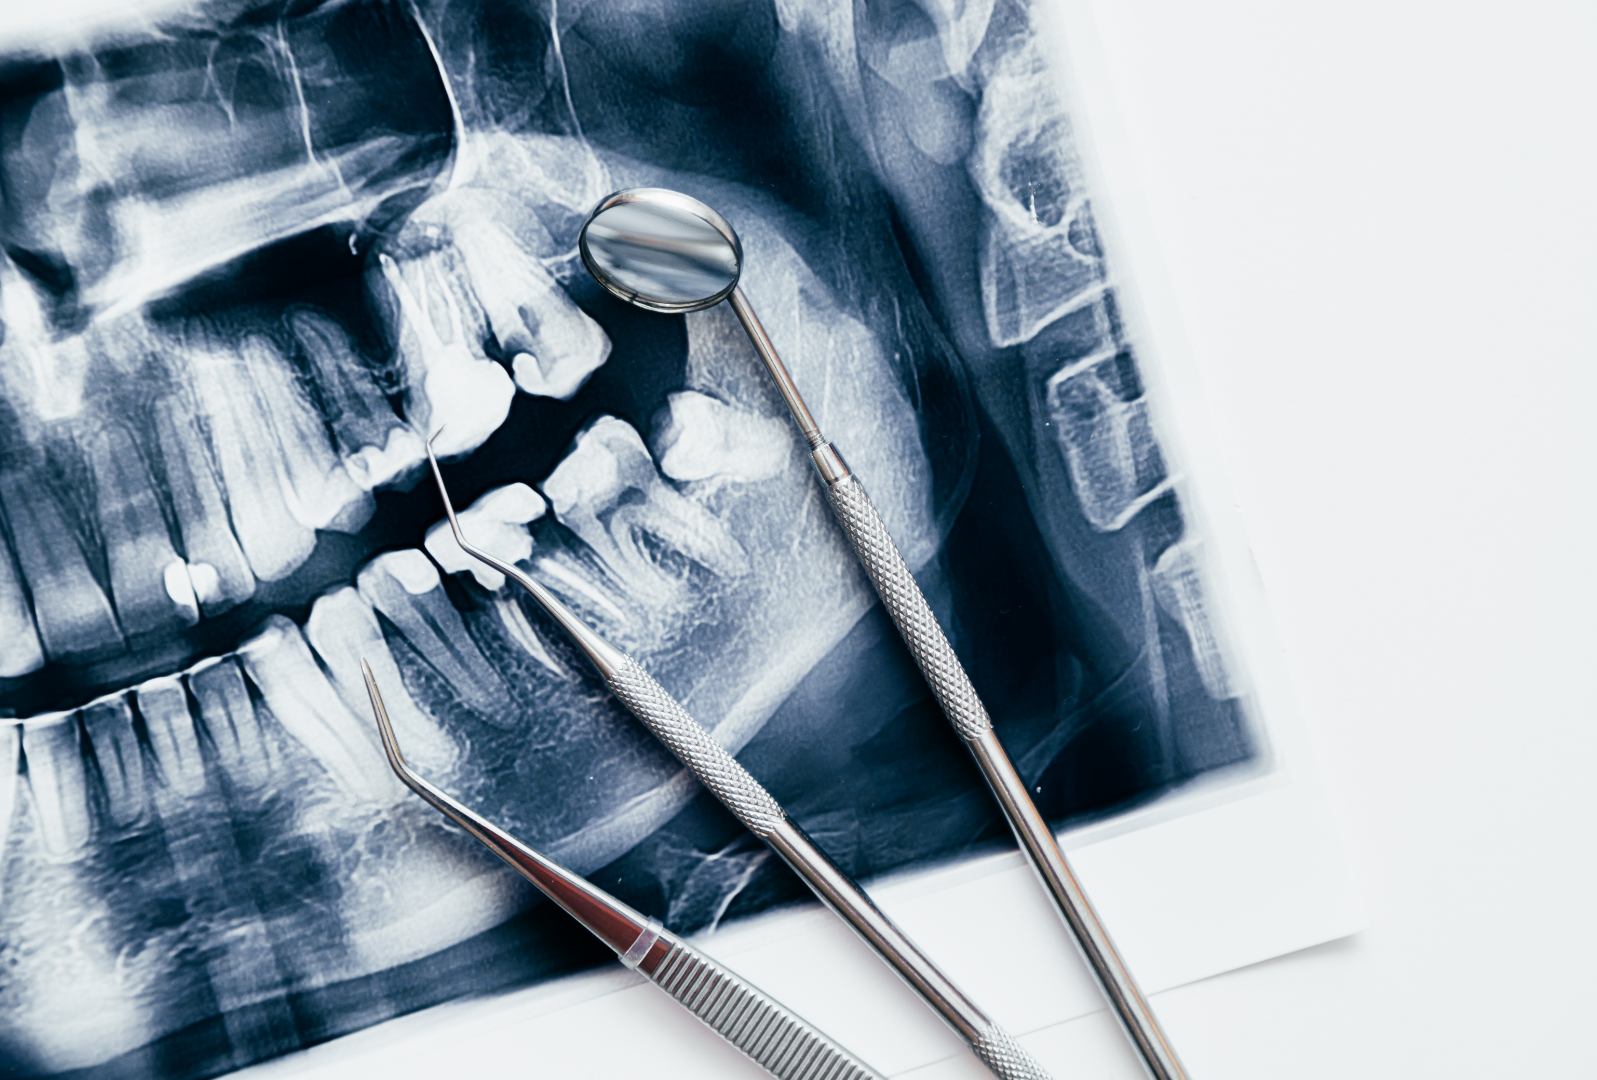

Diagnosis-led consultation for full mouth rehabilitation planning at Cuspid Dental

• Comprehensive oral and functional examination, including digital imaging, diagnostic records and bite & jaw assessment .

Advanced Diagnostic & Planning Protocols – Use of digital imaging, articulated models, and functional analysis to plan restorations that respect jaw position, bite dynamics and long-term stability.